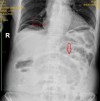

Vai trò của xquang bụng đứng trong chẩn đoán tổn thương tạng rỗng sau các phẫu thuật vùng bụng

03:06 07/09/2020